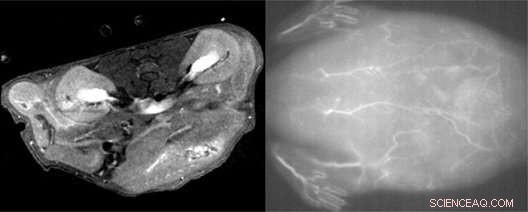

The scientists injected the nanoparticle solution into the tail veins of live mice and were able to obtain high quality MRI (left) and near-infrared fluorescence (right) scans of tissues and blood vessels. Credit: National Institute for Materials Science (NIMS)

The team conducted a series of tests to examine the properties of their nanoparticles. They found that they could be used for obtaining high-quality images of blood vessels in live mice using MRI and near-infrared fluorescence imaging techniques. Further tests showed the nanoparticles exhibited minimal toxicity on mouse fibroblast cells when used in low concentrations. They also have a short half-life, meaning they would be cleared relatively quickly from the body, making them safe for clinical use.